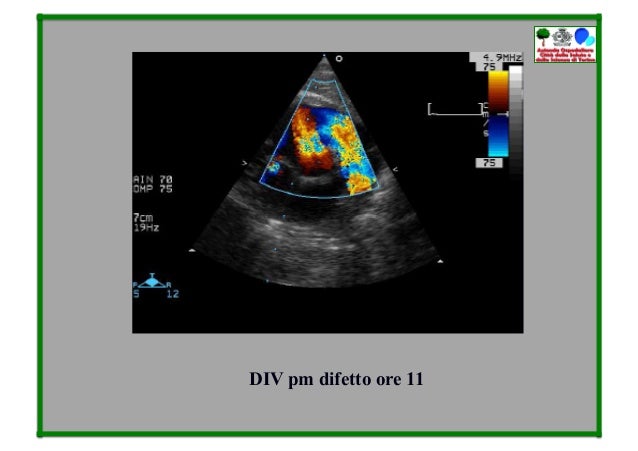

B Difetti Settali Semplici Corso Le Immagini Del Cuore

Med 2000 Eco